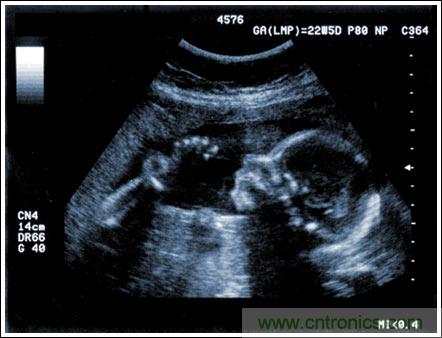

通(tong)過(guo)發(fa)射(she)超(chao)聲(sheng)能(neng)量(liang)進(jin)入(ru)人(ren)體(ti),接(jie)收(shou)並(bing)處(chu)理(li)返(fan)回(hui)的(de)反(fan)射(she)信(xin)號(hao),相(xiang)控(kong)陣(zhen)超(chao)聲(sheng)係(xi)統(tong)可(ke)以(yi)生(sheng)成(cheng)體(ti)內(nei)器(qi)官(guan)和(he)結(jie)構(gou)的(de)圖(tu)像(xiang),映(ying)射(she)血(xue)液(ye)流(liu)動(dong)和(he)組(zu)織(zhi)運(yun)動(dong),同(tong)時(shi)提(ti)供(gong)高(gao)準(zhun)確(que)度(du)的(de)血(xue)流(liu)速(su)度(du)信(xin)息(xi)。傳(chuan)統(tong)設(she)計(ji)中(zhong),構(gou)建(jian)這(zhe)樣(yang)的(de)成(cheng)像(xiang)係(xi)統(tong)需(xu)要(yao)大(da)量(liang)的(de)高(gao)性(xing)能(neng)相(xiang)控(kong)陣(zhen)發(fa)射(she)器(qi)和(he)接(jie)收(shou)器(qi),使(shi)得(de)車(che)載(zai)設(she)備(bei)體(ti)積(ji)龐(pang)大(da)且(qie)價(jia)格(ge)昂(ang)貴(gui)。近(jin)年(nian)來(lai),隨(sui)著(zhe)集(ji)成(cheng)工(gong)藝(yi)的(de)進(jin)步(bu),設(she)計(ji)人(ren)員(yuan)能(neng)夠(gou)獲(huo)得(de)小(xiao)尺(chi)寸(cun)、dichengbenerqiegaodubianxiedechengxiangxitongfangan,bingkedadaojiejindaxingchengxiangshebeidexingnengzhibiao。erxindeshejitiaozhanyirancunzai,jizaijinyibutigaofanganjichengdudetongshitigaoxitongxingnenghezhenduannengli。